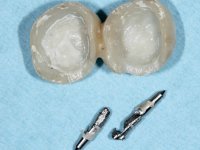

Teeth 17 and 16 were prepared for the fabrication of a 2-element Zr bridge. The impression was performed with a double mixing technique and a monolithic bridge in Zr was made in the laboratory. 4 years later, an abscess appeared in the apical area of tooth 26. It was decided to remove the bridge, remove the intra-radicular posts and retract the endodontic treatments of teeth 17 and 16. The removal of the bridge was carried out by making two cervical cavities. in the palatal area of the bridge and with a microluxator, disinsertion movements were performed. The intra-radicular posts were removed using fine drills and an ultrasound tip. The bridge was provisionally cemented and the patient was referred to a fellow endodontist for endodontic retreatment. After the retreatment, the intraradicular posts were placed again and the bridge was definitively cemented. One year later, a new abscess appears, possibly related to a root fracture. The bridge was sectioned between tooth 27 and 26 and tooth 26 was extracted and the crown of 27 was provisionally cemented. 3 months later, teeth 27 and 25 were prepared and a temporary bridge was made in dual polymerization resin. Then, an impression was made using the double mixing technique and a 3-element bridge in Zr was made in the laboratory. It was permanently cemented in the mouth with resin-reinforced glass ionomer cement.